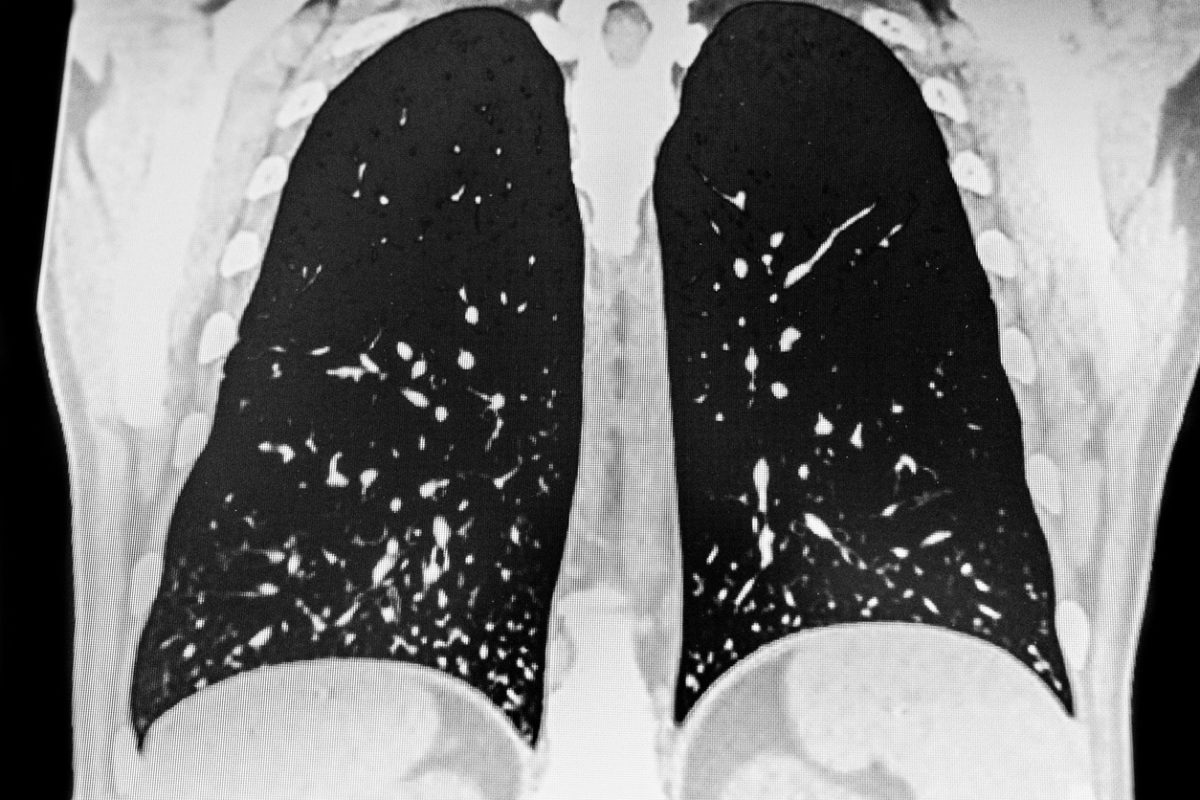

Αξονική τομογραφία θώρακος που δείχνει πολλαπλές μικρές βλάβες, συμβατές με πνευμονική ιστοπλάσμωση